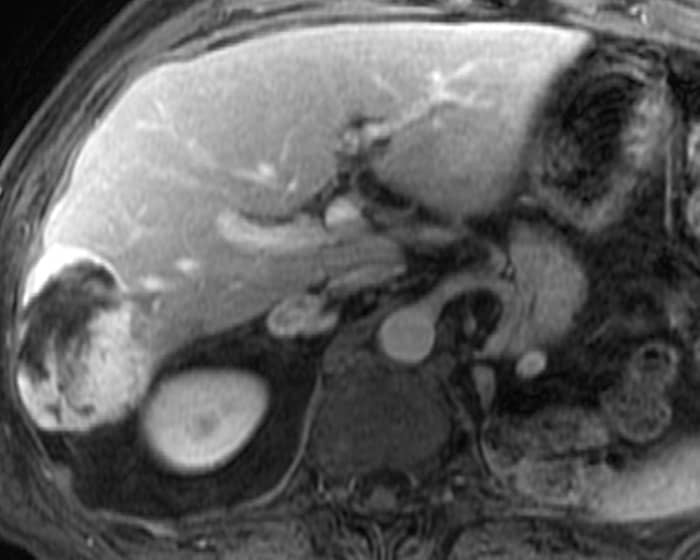

U máu gan

» Thông tin: Nam giới – 70 tuổi.

» Lâm sàng: Tiền sử ung thư thận.